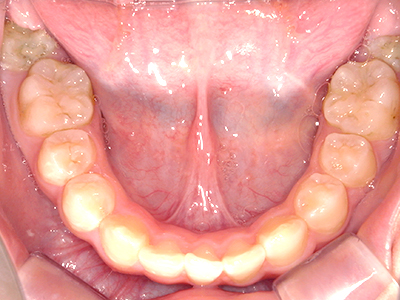

【4】矯正治療

矯正装置を装着し、調整しながら少しずつ歯を移動させ、歯並びを整えていきます。

状態によって家庭でのトレーニングが必要な場合もあり、治療期間も個人差があります。

あくまでも平均値ではありますが、一般的には月1回程度来院頂き、1~2年程度を目安に治療を進めていきます。